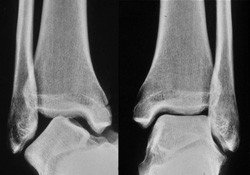

Die Diagnose kann klinisch, das heisst durch eine exakte Untersuchung, gestellt werden. Röntgenbilder sind zum Ausschluss einer Fraktur angezeigt. Die früher routinemässig durchgeführten Stress-Aufnahmen werden für die frische Verletzung nicht mehr durchgeführt.